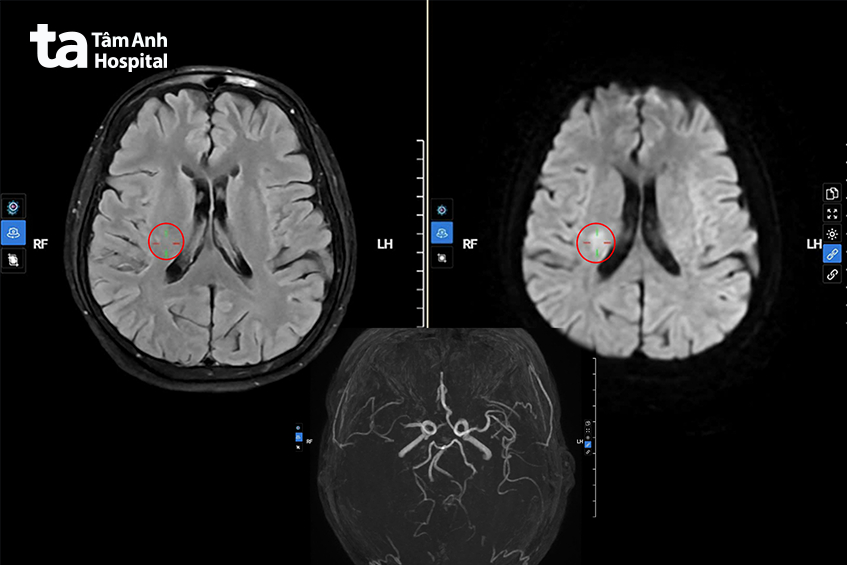

Trong quá trình theo dõi, bác sĩ Long nhận thấy sức cơ tiếp tục giảm, tay và chân lần lượt còn 3/5 và 2/5. Trước nghi ngờ đột quỵ nhồi máu não, dù điểm NIHSS còn thấp và dấu hiệu lâm sàng chưa điển hình, bác sĩ đã chỉ định chụp MRI sọ não để làm rõ nguyên nhân gây yếu liệt.

So với chụp cắt lớp vi tính (CT scan), MRI giúp xác định nhồi máu não rõ ràng và sớm hơn, nhờ các kỹ thuật ghi hình chuyên biệt cho phép phát hiện vùng não thiếu máu ngay từ giai đoạn rất sớm. MRI đánh giá chính xác vị trí, kích thước ổ nhồi máu, hạn chế bỏ sót các tổn thương nhỏ hoặc nằm sâu như thân não, tiểu não, từ đó hỗ trợ bác sĩ ra quyết định điều trị kịp thời, tránh bỏ lỡ “giờ vàng”.

Kết quả MRI xác định bà Lành đang gặp tình trạng nhồi máu não cấp sớm, giờ thứ 3. Ngoài ra, động mạch máu não của bà cũng bị hẹp nặng, tắc hoàn toàn cộng thêm sự xuất hiện của một túi phình mạch máu não.